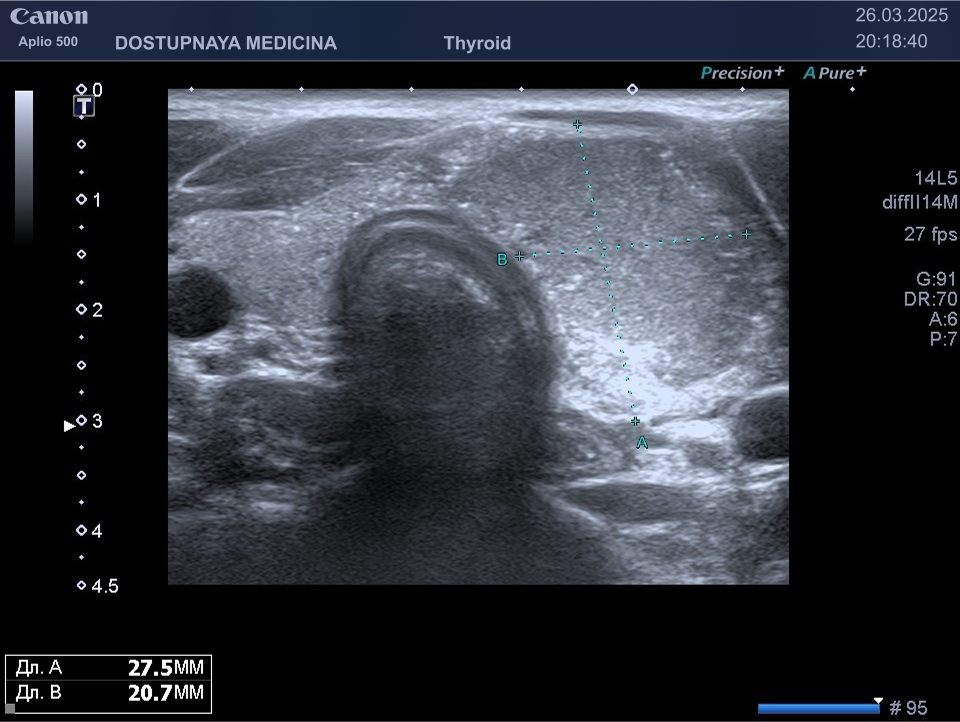

В ультразвуковой диагностике существует классификация образований щитовидной желзы по TIRADS, которая по различным критериям определяет степень онкоопастности того или ионого узла. При оценке учитывается эхоструткура образования ( кистозная, губчатая, солидная или солидно-кистозная), эхогенность ( анэхогенное, гиперэхогенное, гипоэхогенное), пространственная ориентация горизонтальная, вертикальная, неопределённая), контуры образования (ровные, дольчатые, зазубренные с острыми углами), наличие эхогенных включений( макрокальцинаты, микрокальцинаты, периферическая кольцевидная кальцификация). В зависимости от этих критериев выделяют различные категориии объёмных образований в щитовидной железе:

TIRADS 3 – низко подозрительное образование, требующие динамическое наблюдение и тонкоигольной биопсии при размерах узла больше 2.5 см.

TIRADS 4 – умеренно подозрительное образование, требующие динамическое наблюдение и тонкоигольной биопсии при размерах узла больше 1.5 см.

TIRADS 5 – высоко подозрительное образование, требующие динамическое наблюдение и тонкоигольной биопсии при размерах узла больше 1 см.

Большинство узловых образований в щитовидной железе не нуждаются в лечении и требуют лишь наблюдения путём повторного ультразвуковых исследований.

При подозрении на озлокачествление и увеличении узла в размерах требуется тонкоигольная пункционная биопсия с полседующим цитологическим исследованием, полученного материала.